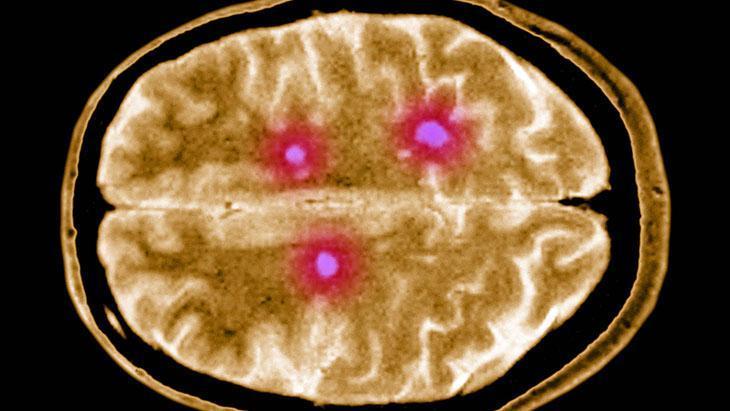

MS’in tek bir tanısal yöntemi yoktur. Genellikle hastanın öyküsü, nörolojik muayene bulguları, beyin ve omurilik MR sonuçları, bazı durumlarda belden sıvı alınarak bakılan beyin ve omurilik sıvı bulguları ve bazen de elektrofizyolojik testler bir arada incelenerek tanı konur.

Öncelikle şunu belirtmek gerekir ki bu hastalığa "multipl" denmesinin nedeni, beyin ve omuriliğin birçok farklı alanını etkilemesindendir. Aniden ortaya çıkabilir ya da kaybolabilir. Belirtileri çok çeşitlidir. Hastadan hastaya değişiklik gösterebileceği gibi aynı hastada da zaman içinde farklılaşabilir.

"Skleroz" denmesinin nedeni ise hastalığın beyin ve omuriliğin hasarlı alanlarında sklerozan plaklar yani sertleşmiş dokular oluşturmasıdır. Özetle MS, merkezi sinir sistemini oluşturan beyin ve omurilik üzerinde yıkıcı etkileri olan, kişinin yaşamsal fonksiyonlarını bozan ve ataklarla seyreden bir hastalıktır.